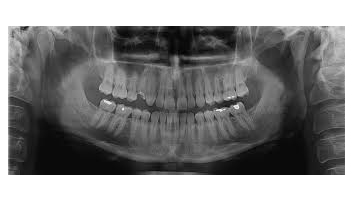

- Rx des os et des articulations